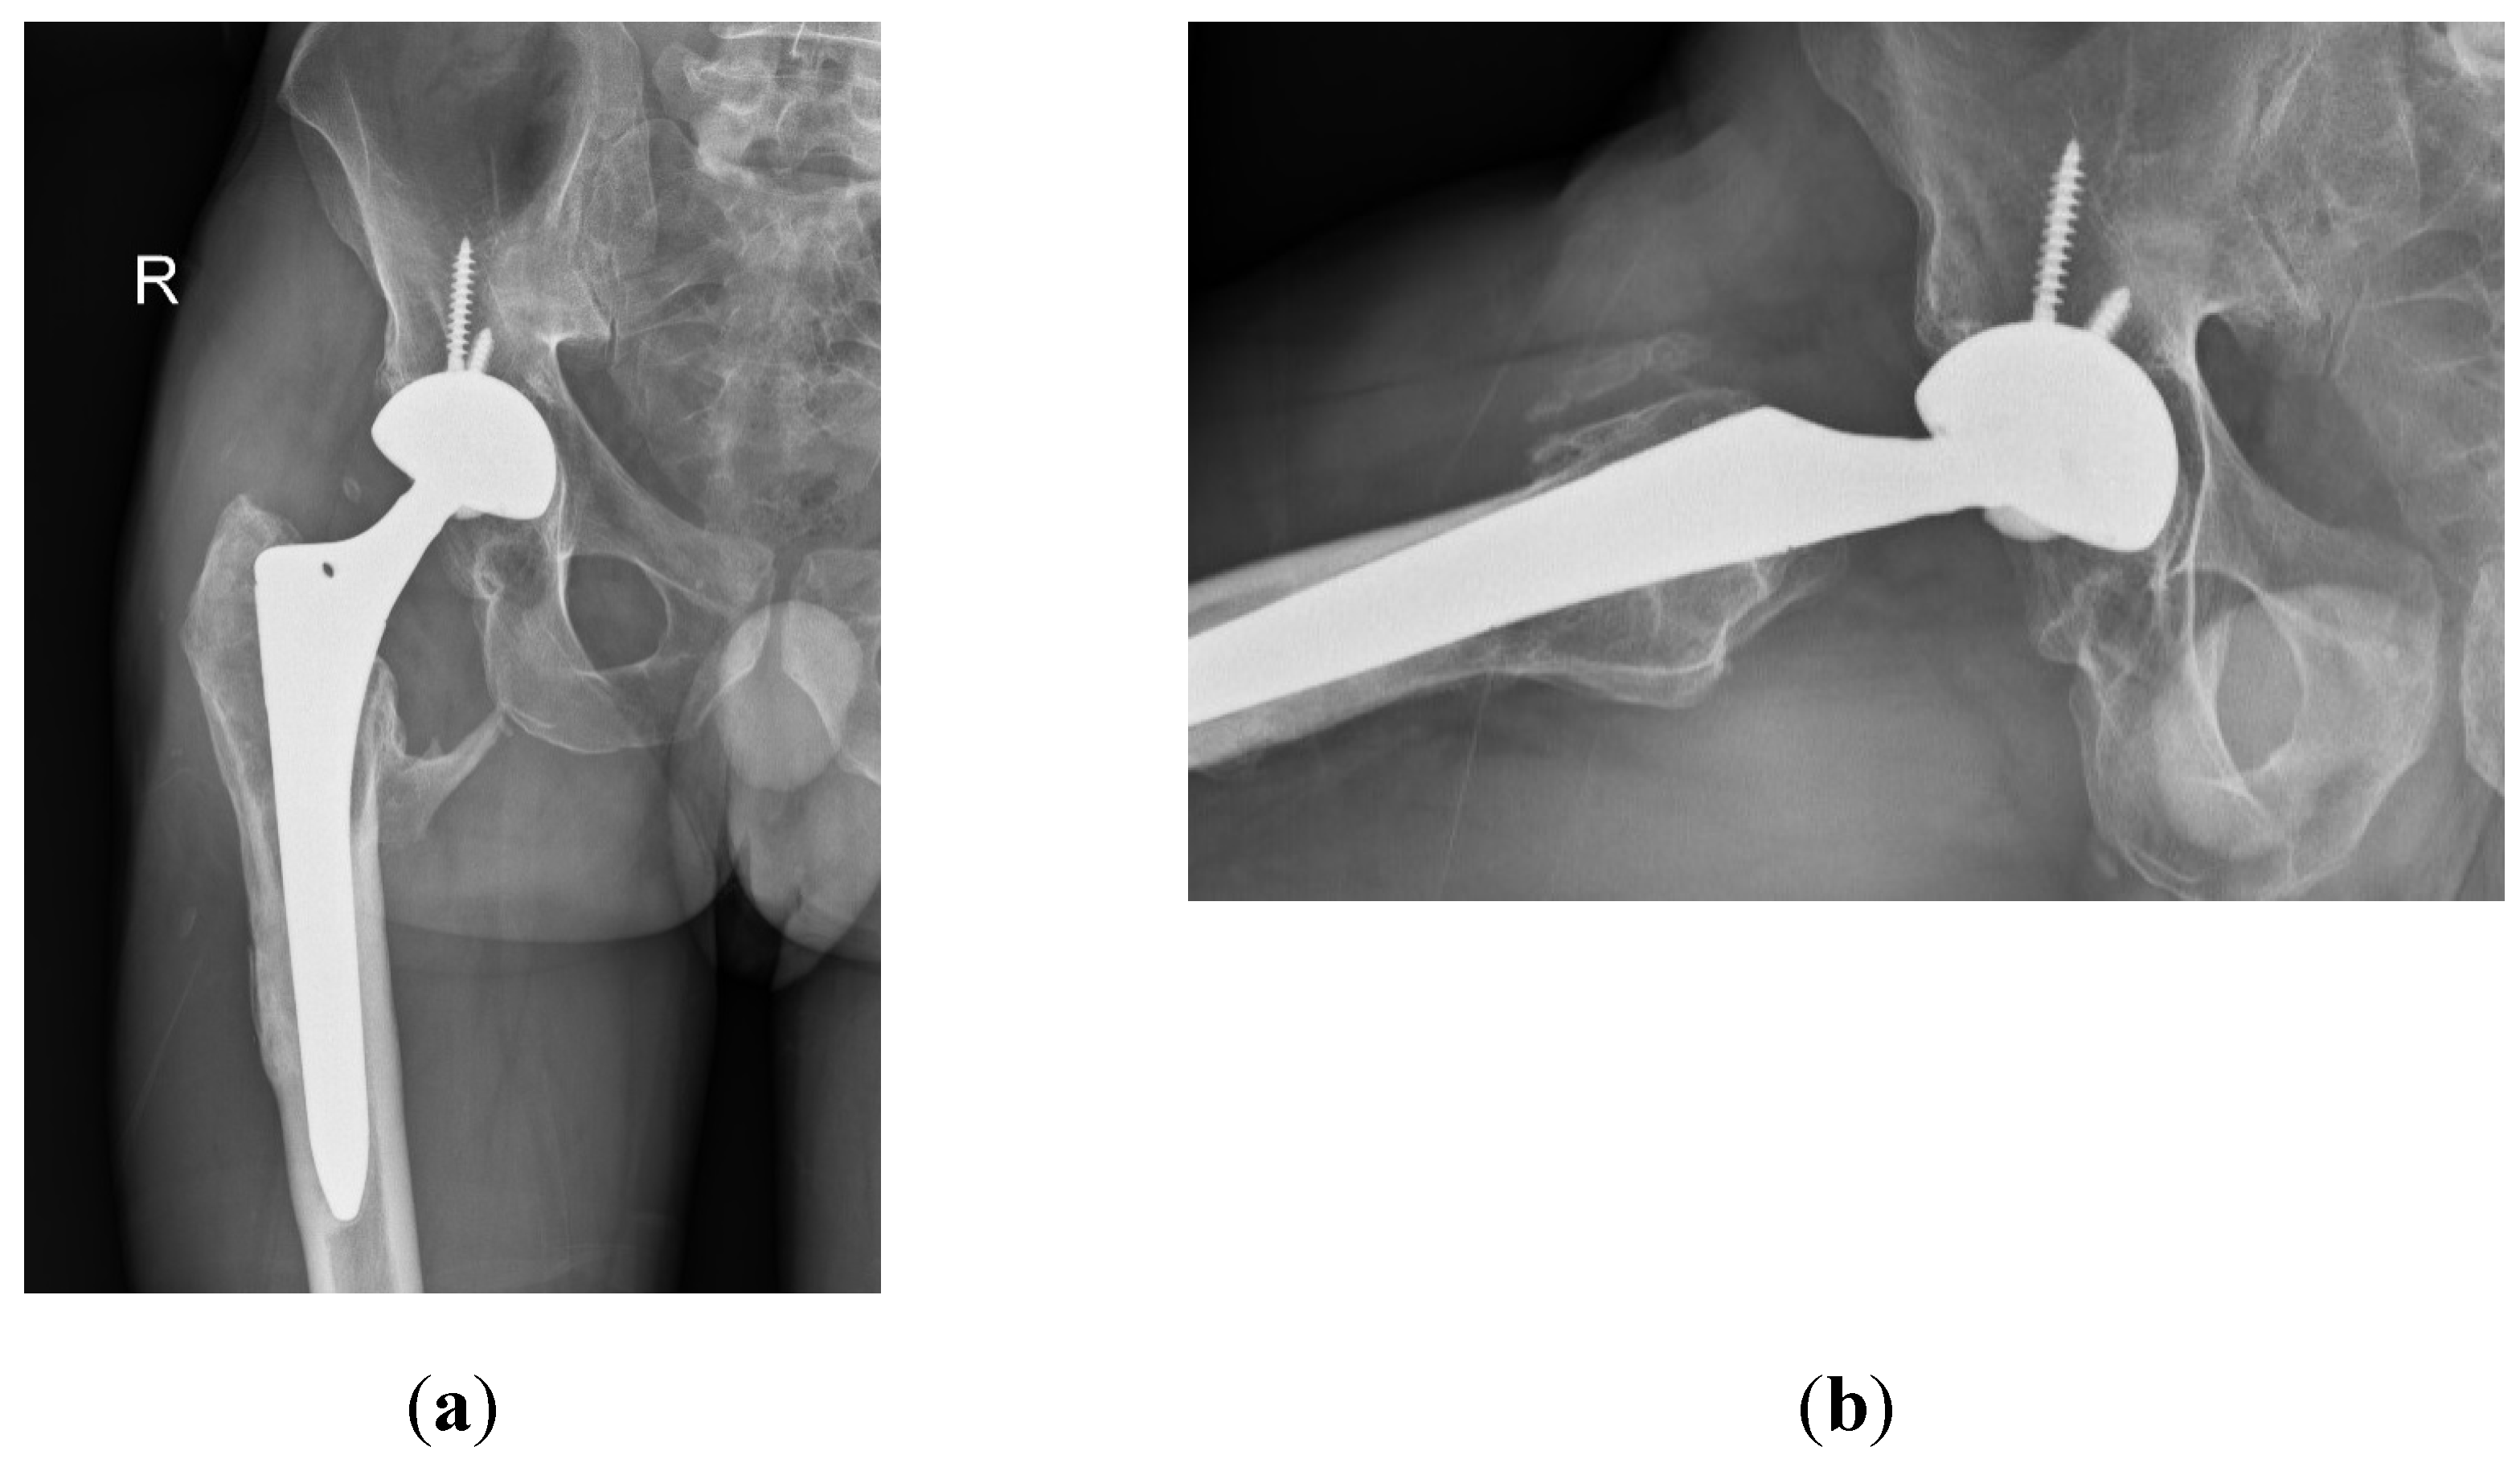

Despite the absence of pain, the patient reported unusual sounds in the hip during weight-bearing, linked to the ceramic-on-ceramic (CoC) bearing. Standard radiographs of the right hip were deemed normal, as depicted in the first available postoperative X-ray (Figure 1). Therefore, no further evaluation or specific treatment was advised for the patient.

Figure 1. Radiographs of the patient’s right hip 8 years after primary THA. (a) Antero-posterior view; (b) Lateral view.